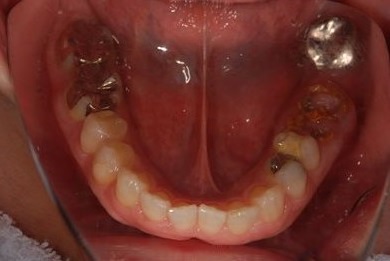

抜歯即日スピードインプラント治療+セラミック治療+歯肉歯槽骨整形術

| 治療方針 | 左下欠損部と保存不能の歯を抜歯し、インプラント治療にて機能的・審美的回復を行う。 | ||||||||||||||||||||||||||||||||

| 治療内容 | インプラント2本(抜歯即日スピードインプラント)、ハイブリッドセラミッククラウン2本、歯肉歯槽骨整形術 | ||||||||||||||||||||||||||||||||